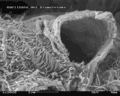

الكبيبة.- صورة بالمجهر الإلكتروني الماسح للكبيبة في الفأر (تكبير 1000x)

- صورة بالمجهر الإلكتروني الماسح للكبيبة في الفأر (تكبير 5000x)

- صورة بالمجهر الإلكتروني الماسح للكبيبة في الفأر (تكبير 10,000x)